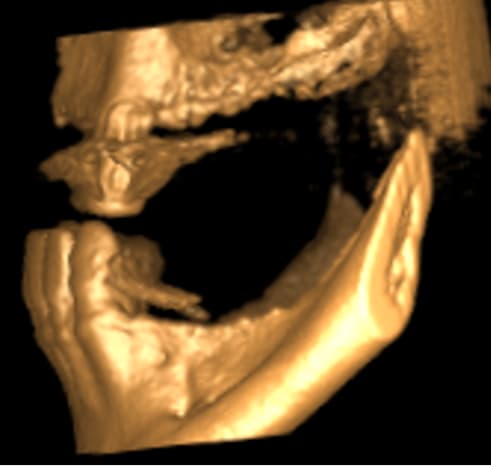

Au maxillaire il faut faire une implanto totale et stt ne pas garder les canines

A la mandibule faut disker mais ça va

PS il faut d abord faire réaliser des modèles stéréolithographiques par Materialise pour se prononcer au final

Je rentre cette apm et je tente de charger ton examen cone beam